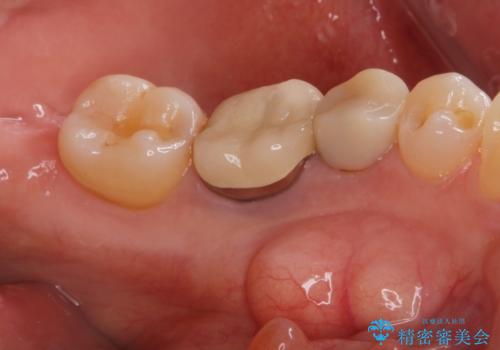

骨隆起除去

治療症例の内容

- 骨隆起が舌にあたり不快感があるので骨隆起をとりたくて来院。

静脈内鎮静麻酔下で骨隆起を除去を行いました。